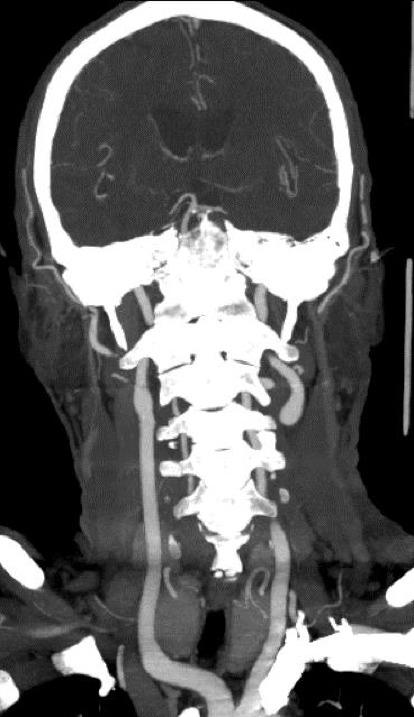

边缘带淋巴瘤(MZL)是一种惰性淋巴瘤,很少累及中枢神经系统(CNS)。边缘性B细胞淋巴瘤(CBL-MZ)是一种恶性前病变,指的是外周血中存在克隆B细胞,但没有器官肿大、淋巴结病变或其他已建立淋巴瘤的特征,可能罕见地进展为MZL,因此除了积极监测外不需要治疗。一名54岁男性,先前诊断为CBL-MZ,表现为多次复发性皮质下缺血性中风。在反复评估中,没有证据表明进展为明显的MZL或二次转化。他的中风对抗血栓治疗和抗凝治疗无效。由于没有明显的心血管危险因素,因此进行了广泛的评估,排除了继发性原因,如心脏栓塞、血栓前状态或全身性血管炎。最后,他被发现有淋巴瘤累及脑脊液。复发性缺血性中风归因于肿瘤性脑膜炎引起的脑小血管病变,这促使化疗的开始,导致中风复发的显著停止。该病例强调了考虑中枢神经系统受累的重要性,即使是在惰性或癌前淋巴瘤中,当这些患者出现“隐源性”复发性卒中,对标准的继发卒中预防治疗似乎难治性。我们还描述了复发性缺血性卒中的方法,影像学对确定卒中机制的重要性,以及小血管脑动脉病变的方法。

Marginal zone lymphoma (MZL) is an indolent lymphoma that rarely involves the central nervous system (CNS). Clonal B-cell lymphomatosis of marginal zone origin (CBL-MZ) is a premalignant condition referring to the presence of clonal B cells in the peripheral blood without evidence of organomegaly, lymphadenopathy or other features of established lymphoma, which may uncommonly progress to MZL, and as such does not require treatment beyond active surveillance. A 54-year-old male with previously diagnosed CBL-MZ presented with multiple recurrent subcortical ischaemic strokes. There was no evidence of progression to overt MZL or secondary transformation on repeated evaluation. His strokes proved refractory to antithrombotic therapy and anticoagulation. The absence of significant cardiovascular risk factors led to an extensive evaluation which excluded secondary causes such as cardioembolism, prothrombotic state or systemic vasculitis. Eventually, he was found to have lymphomatous involvement of the cerebrospinal fluid. The recurrent ischaemic strokes were attributed to a cerebral small vessel vasculopathy from neoplastic meningitis, which prompted the initiation of chemotherapy, leading to a remarkable cessation of stroke recurrence. This case highlights the importance of considering CNS involvement even in indolent or premalignant lymphomas when these patients present with "cryptogenic" recurrent strokes that appear refractory to standard secondary stroke prevention therapy. We also describe the approach to recurrent ischaemic stroke, the importance of imaging to determine the stroke mechanism, and the approach to small vessel cerebral arteriopathies.